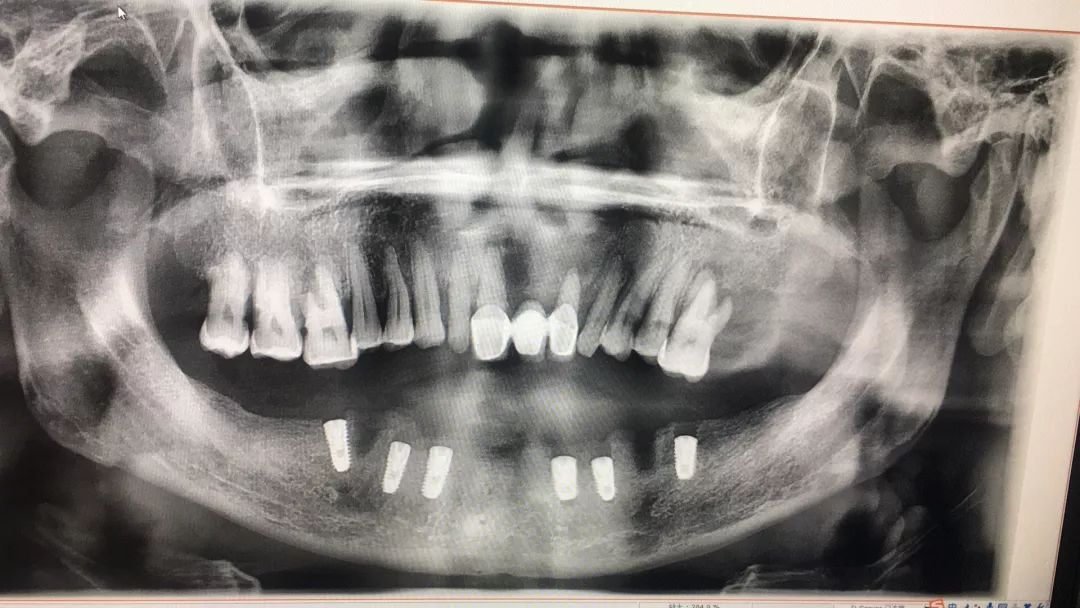

在7月18日上午,由广大口腔的王利晖主任为何叔做了下半口的种植手术,拔除松动牙齿后植入6颗种植体。术前何叔对工作人员说:“先种下半口的,上半口迟些再种。要是效果好,我还是认定广东省爱牙工程和广大口腔。